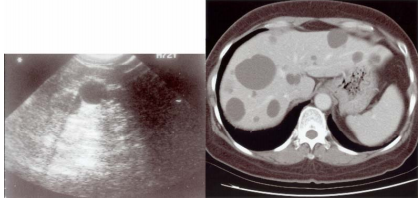

74 一位 45 歲男性為 B 型肝炎帶原人士,日昨到醫院做健康檢查,肝臟超音波掃描和 CT 掃描影像如圖所 示。則張先生最有可能罹患:

(A)囊腫(hepatic cyst) (B)肝硬化合併壞死(liver cirrhosis with necrosis) (C)海綿狀血管瘤(cavernous hemangioma) (D)肝細胞癌(hepatocellular carcinoma)